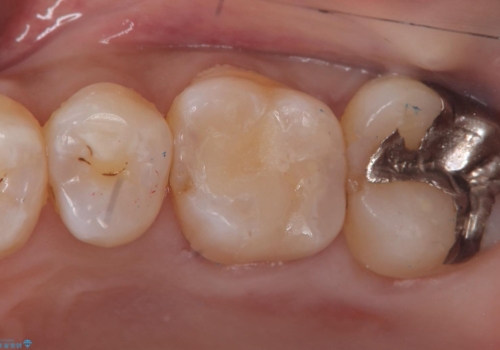

- 主訴:銀の詰め物が外れてしまった

保険適応のメタルインレーが脱離し、中が少し虫歯になっていたため審美性も良いセラミックインレーでのやり替えとなりました。

旧インレー窩洞内のカリエスと裏層を除去し、新たにCR裏層したうえでセラミックインレー修復を行いました。セラミックインレーセット時は、ラバーダム防湿を行っています。